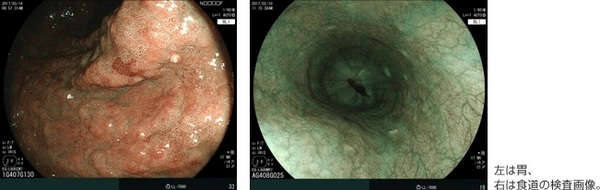

富士フイルム(株)は、光源に波長の異なる2種類のレーザーを用いた内視鏡システム「LASEREO(レザリオ)」シリーズの新たなラインアップとして、「LASEREO 7000システム」を2017年5月15日より、富士フイルムメディカル(株)を通じて発売する。「LASEREO」は、波長の異なる2種類のレーザー光の発光比率を変え、粘膜表層の微細な血管や構造などを強調して表示する「Blue LASER Imaging(BLI)機能」や、画像の赤色領域のわずかな色の違いを強調して表示する画像処理機能「Linked Color Imaging(LCI)」などにより、微小な病変の観察をサポートする内視鏡システムである。2012年9月の発売以来、特に早期がんに特徴的な粘膜表層の微細血管などの変化の観察で、医療機関から高い評価をいただいている。

今回発売する「LASEREO 7000システム」は、プロセッサー「VP-7000」とレーザー光源装置「LL-7000」で構成される内視鏡システムである。同社のレーザー制御技術をさらに進化させることで、粘膜表層の血管や構造の観察に適したBLI機能を使用して中景・遠景を観察する際の観察画像の明るさを向上させた。視認性を高めることで、より精細な観察をサポートする。

同社のレーザー制御技術をさらに進化させることで、粘膜表層の血管や構造の観察に適したBLI機能で中景・遠景を観察する際、観察画像の明るさが向上。視認性を高めることで、より精細な観察をサポートする。